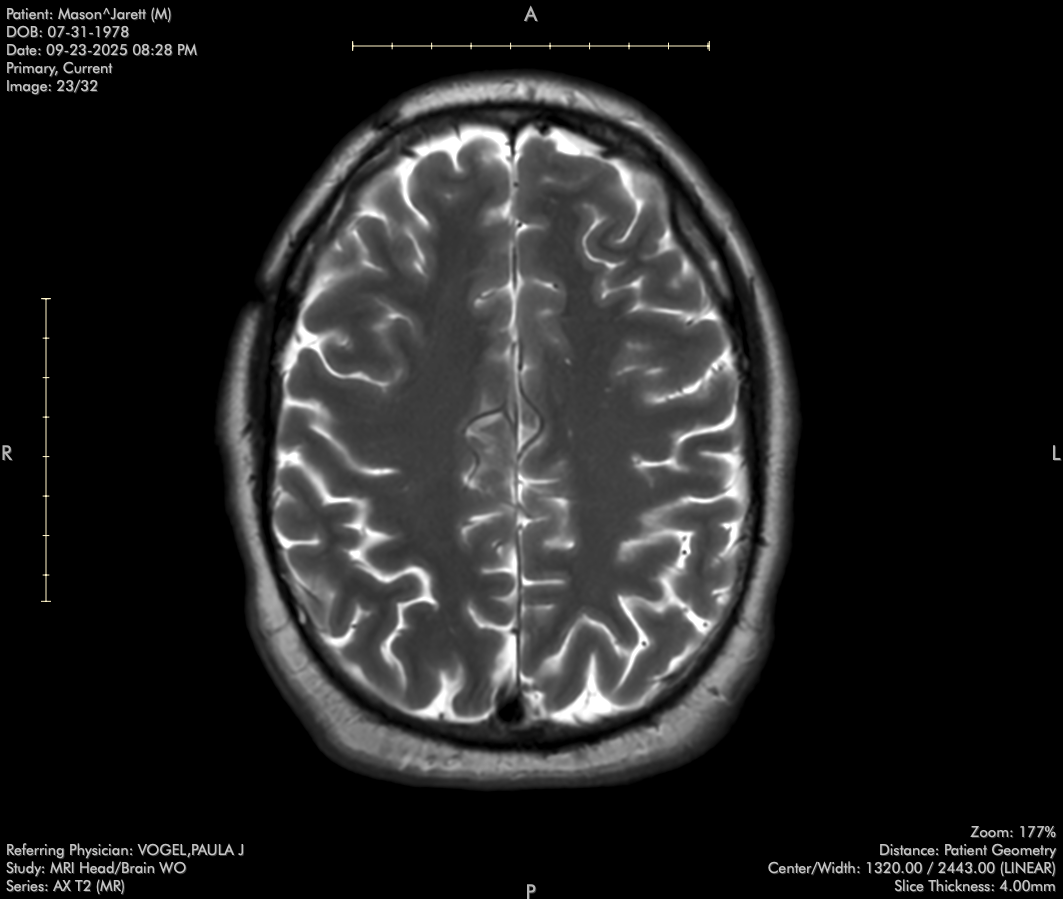

In late August, I was struck by a car while riding my moped to a therapy appointment for my concussion. While incredibly lucky to walk away from the accident, my doctors are concerned about its impact on my recovering brain.

So my recovery has been set back… more doctor appointments, imaging, and therapy in my future, but I’m in good hands. Thank you all again for your thoughts and support, and thank baby Jesus for baseball (and a loving wife) during times like this!